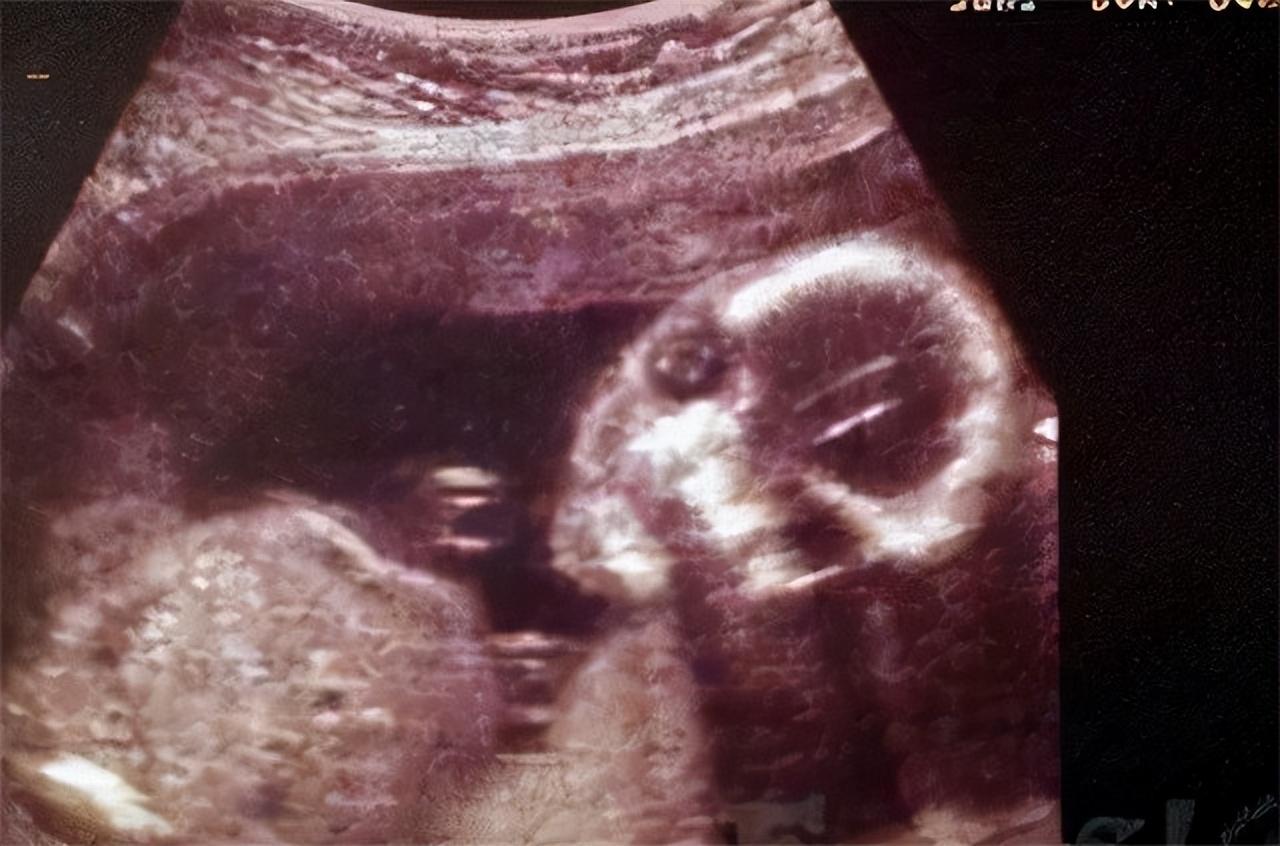

“26公分左右。” 医生一边看着X光片,一边估算着胎儿的大小。

去往眉山市第一人民医院后,黄家人获得了一样的结果,也是确认黄义均腹中存在胎儿,而且尺寸也确认了,就是25到26公分左右。

根据对图片的细致分析,徐先明医生说道: “你看这个图片,胎儿是和脊柱是重叠在一起的,这说明他是在腹腔里的,如果是在子宫内的话,他不应该和这个脊柱重叠起来。”

这一结果说明黄义均的腹中胎儿乃是腹腔妊娠。